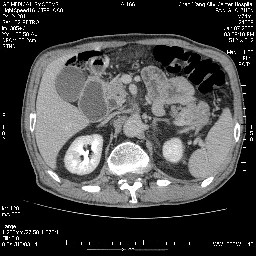

女,74岁,呕吐10余日

壶腹部的占位性病变,考虑为十二指肠癌并梗阻,但脾内多发性低密度区为转移吗?

还有胃、脾之间可见有侧支循环建立。左肾盂积水。

考虑来源于十二指肠水平段的恶性占位,侵及周围组织,特别是胰腺,可见区域淋巴结肿大,左侧下腔静脉畸形。

十二指肠水平段腔内占位伴梗阻,中等度较为均匀的强化,洗脱慢,区域淋巴结显示增多,符合腺癌表现。下腔静脉变异。

十二指肠降段扩张,水平段狭窄成鼠尾状,肠壁明显增厚,胰腺勾突增大成不均匀强化,其内可见低密度区,胆囊增大,1十二指肠水平段腺癌侵犯胰腺勾突可能大,2胰腺癌侵犯十二指肠(只有胆囊增大没有肝内外胆管扩张不好解释)代除外.

上消化道造影见十二指肠结节状充盈缺损,ct增强十二指肠壁局限性增厚并强化,考虑十二指肠壶腹癌?

十二指肠降段扩张,水平段狭窄成鼠尾状,肠壁明显增厚,胰腺勾突增大成不均匀强化,其内可见低密度区,胆囊增大,1十二指肠水平段腺癌侵犯胰腺勾突可能大,2胰腺癌侵犯十二指肠 。

今日手术结果:胰腺钩突癌侵犯十二直肠,腹腔淋巴结转移.